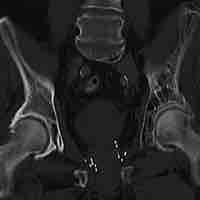

Rheumatism and Arthritis

Rheumatoid arthritis is a chronic, systemic inflammatory disorder that affects many tissues and organs, but mainly attacks flexible joints.